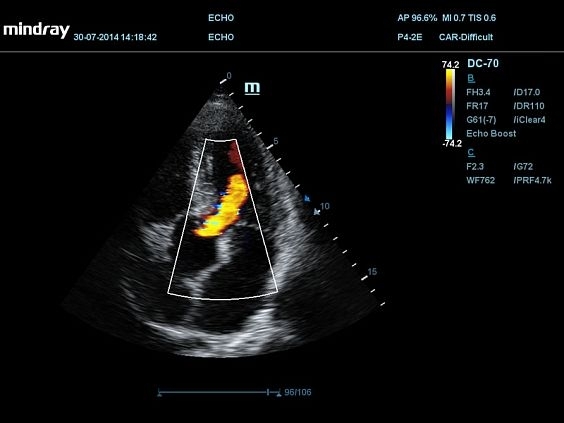

Mindray DC-70 Pro — это высокотехнологичный ультразвуковой аппарат, созданный для обеспечения точной диагностики и максимальной эффективности в работе. Он оснащён инновационными технологиями визуализации, такими как тканевая гармоника и адаптивное подавление шумов, что позволяет получать детализированные и чёткие изображения для точных клинических решений.

• Поддержка множества режимов сканирования, включая B, M, цветной и энергетический доплер, что делает аппарат универсальным для различных исследований.

• P4-2E — секторный фазированный датчик;

• LVO contrast — исследование левого желудочка с контрастированием (доступно на датчиках SP5-1E, P4-2E);